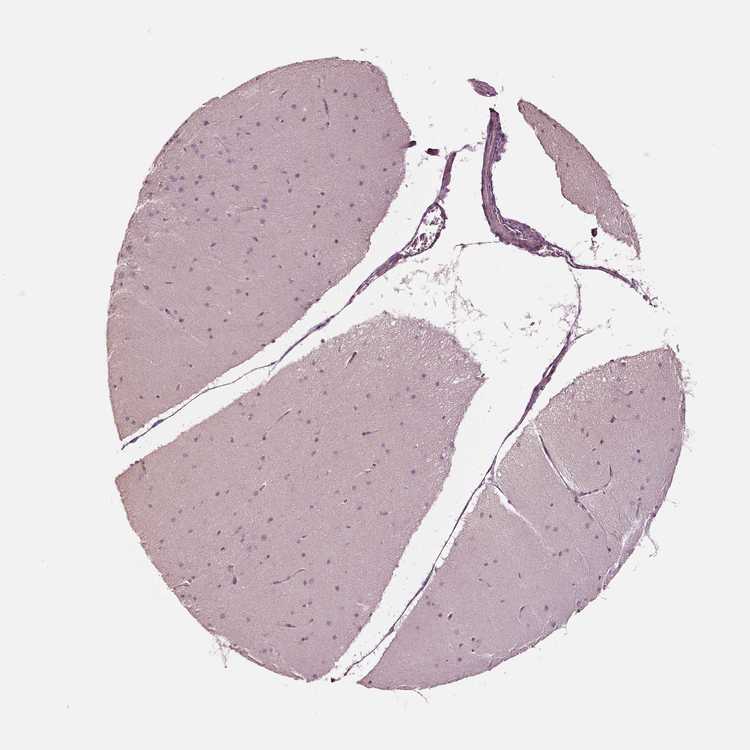

BRAIN CEREBELLUM Show tissue menu

CEREBELLUM - Antibody stainingi

Antibody staining in the annotated cell types in the current human tissue is reported as not detected, low, medium, or high, based on conventional immunohistochemistry profiling in selected tissues. This score is based on the combination of the staining intensity and fraction of stained cells.

Each image is clickable and will lead to virtual microscopy that enables deeper exploration of all samples and also displays staining intensity scores, fraction scores and subcellular localization as well as patient and tissue information for each sample.

Antibody HPA028808

Purkinje cells Not detected

Cells in granular layer Not detected

Cells in molecular layer Not detected